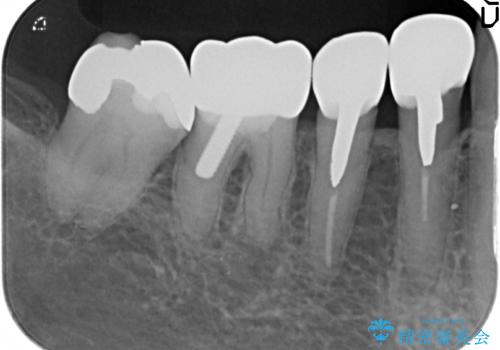

大臼歯 再根管治療

- 銀歯を白くしたいとの希望で来院されました。

せっかく銀歯を白くしても後々根管治療が必要になり、また壊して再治療を行うことを避けたいとの事でしたので、再根管治療から行っていきます。

ただ銀歯を白くするのではなく長期的な予後には歯の内部、根管治療の成功が必要不可欠です。